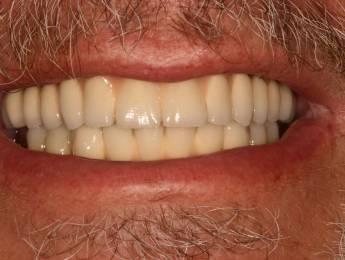

1. eset

A páciens fogágybetegség miatt érkezett hozzánk. A felső fogak menthetetlen állapotban voltak. All on 6 megoldásként a felső fogak eltávolításakor 6 implantátum került beültetésre és a páciens azonnal egy fix ideiglenes hidat kapott. 4 hónapos gyógyulási idő után készült el a felső fémkerámia leplezésű körhíd.